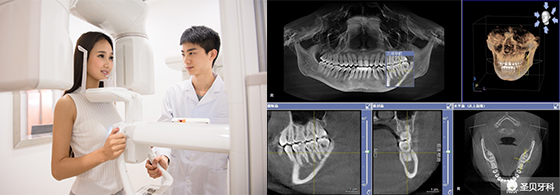

【技术设备】

医疗设备和技术,是一切医疗行为开展的基础。先进的诊疗设备,使治疗过程能做到精准精细。

特别是在口腔种植牙、口腔正畸、口腔修复等治疗科室上尤为重要,在口腔内科——拔牙、补牙、根管治疗项目上,也能避免治疗不彻底的情况。

圣贝牙科连锁——高端牙科自主品牌。在技术上,美颜正畸系统、亲贝美齿系统、炫彩美白系统、ZEISS数字显微修复系统等JCI认证技术设备。